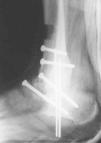

Se observaron 2 (5,26%) casos que precisaron de varias reintervenciones y lavados con el procedimiento de Papineau en 3 tiempos (fig. 11).

Fig. 11. --Osteomielitis. Técnica de Papineau en 3 tiempos. Resultado a los 24 meses. Artrodesis consolidada sin infección.

Fig. 11. --Osteomyelitis. Papineau's technique in 3 stages. Results at 24 months. Consolidated arthrodesis without infection.

Hemos realizado tan sólo 1 caso debido a una pseudoartrosis (figs. 11 y 12), que se complicó posteriormente con una osteomielitis aguda por lo que se le realizó los 3 tiempos de Papineau. En líneas generales, la talectomía no ha demostrado buenos resultados.